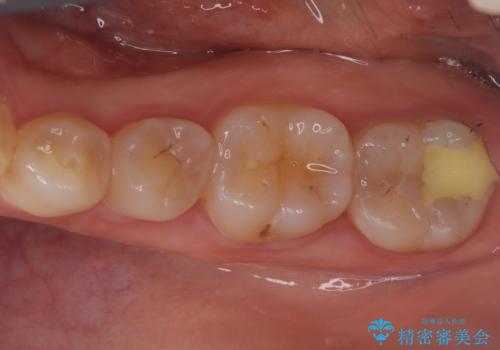

歯と歯の間の虫歯もセラミックで再発防止

担当医 河口智英